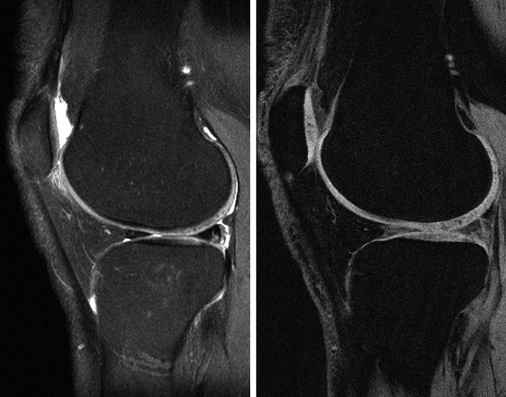

Hierfür sind insbesondere 2 Sequenztypen geeignet. Die erste ist die moderat T2-gewichtete Turbo-Spin-Echo Sequenz, in der der Knorpel ein intermediäres Signal im Vergleich zur Gelenkflüssig-keit zeigt (  Abb. 7 , links). Ihre Sensitivität zur Detektion von Knorpelbinnenläsionen beträgt 94 % (Resnick et al. 2006). Sie wird typischerweise zweidimensional in unterschiedlichen Ebenen akquiriert, in Abhängigkeit davon, welches Gelenk betrachtet werden soll.

Neue technische Entwicklungen erlauben inzwischen auch eine dreidimensionale Akquisition dieser Sequenztechnik, die eine nachträgliche freie Reformation der Bilddaten in allen Raumrichtungen ermöglicht (Notohamiprodjo et al. 2009, 2012).

Eine komplementäre Sequenz, die eine sehr gute Darstellung der Knorpeldicke und des Knorpelvolumens darstellt, ist die T1-gewichtete fettunterdrückte oder wasserangeregte 3D-Gradientenechosequenz (s. Abb. 7, rechts). Auch diese lässt sich in den unterschiedlichen Raumebenen nachträglich reformatieren. Der Knorpel bietet in dieser Technik eine sehr hohe Signalintensität und lässt sich daher sehr gut von dem umgebenen Strukturen, insbesondere vom subchondralen Knochen abgrenzen (Graichen et al. 2000; Glaser et al 2001). Die Sensitivität dieser Sequenz für Knorpelläsionen beträgt ca. 93 %, wobei sie eher geeignet ist Dickenveränderungen darzustellen und nur eingeschränkte Beurteilbarkeit der Matrix selbst bietet, für die eher eine moderat T2-gewichtete Sequenz genutzt werden sollte (Resnick et al. 2006).